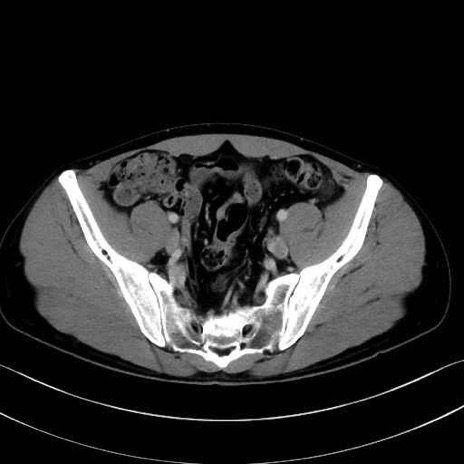

内閉鎖筋 (Obturator internus)